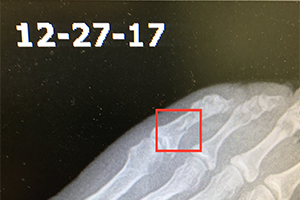

A female patient presented with a broken toe resulting from a slip on the ice December 20th, 2017. This finding was confirmed with x-ray the following morning. She started a regimen with the Wei Fastt patches. Additionally, she started on 1 capsule, 3 times daily of the Wei product Martial. This product helps to activate blood circulation in the bones to expedite the healing process of the Fastt patch. Furthermore she also added in a vitamin product, Intenzyme Forte from Biotics Research Corporation, to help reduce swelling and inflammation. Along with these therapies she increased her calorie and total protein intake to address a nutritional need in her body for further speed in healing.